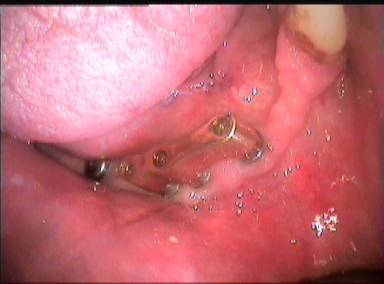

si je vous dis que je n'ai pas d'échec, je vous prie de me croire, bande d'ignorants. voilà un cas mené de main de maître: je voulais faire un bridge fixe classique partiel sur implants à la mandibule. absolument aucun souci: si j'ai déposé l'implant en 42, c'est juste parce que j'avais envie, le laisser donnait au travail un goût d'inachevé. quant à l'implant distal, j'ai testé, exprès, un nouveau concept à la mode qui s'appelle péri-implantite. j'ai juste voulu voire comment se comporte un implant qui perd les deux tiers de son ancrage. nous étions persuadés, mon patient et moi, que les bridges fixes étaient d'un banal, et qu'il serait plus in de faire une prothèse mobile. voilà.